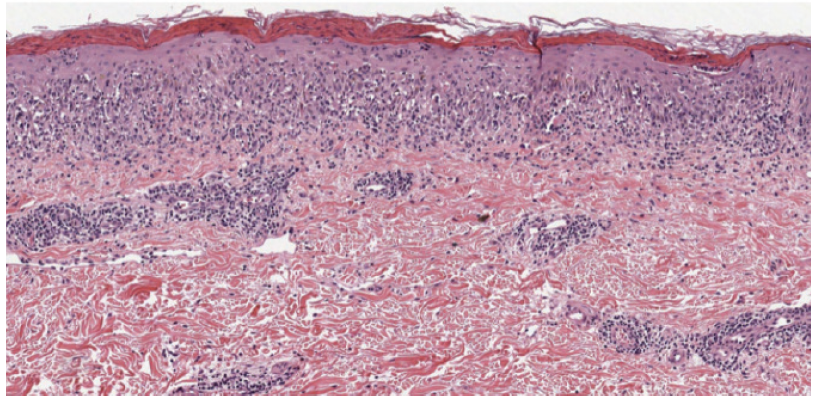

PLC presents as recurrent crops of spontaneously regressing erythematous to purpuric papules. These papules are commonly scaly as compared with the lesions in PLEVA, which are commonly crusted, ulcerated, and occasionally vesicular or pustular. The lesions often regress over weeks to months; however, patients will commonly relapse. It is hypothesized that the distribution of the lesions is more important than the acute or chronic nature. Patients with a diffuse distribution of lesions tend to have a shorter average disease course of approximately 11 months, compared with patients with a peripheral distribution who have a longer average disease course of approximately 33 months.1 Diagnosis requires histopathologic evaluation. PLC exhibits a superficial perivascular interface dermatitis. Lymphocytes predominate in the infiltrate, although neutrophils are sometimes present as well. Within the epidermis, there is focal parakeratosis and evidence of damage that ranges from edema to extensive epidermal necrosis. Frequently, there is extravasation of erythrocytes. All these changes are blunted in more chronic lesions.1

The patient had a punch biopsy from the left thigh that was consistent with PLC (Figures 5–8). She was started on 3 courses of azithromycin over 6 weeks and referred for phototherapy. She received phototherapy 3 times weekly for approximately 1.5 months. After this course of phototherapy, she had developed no new lesions and old lesions were healing, although they did exhibit post inflammatory hyperpigmentation. She was started on doxycycline 100 mg daily.